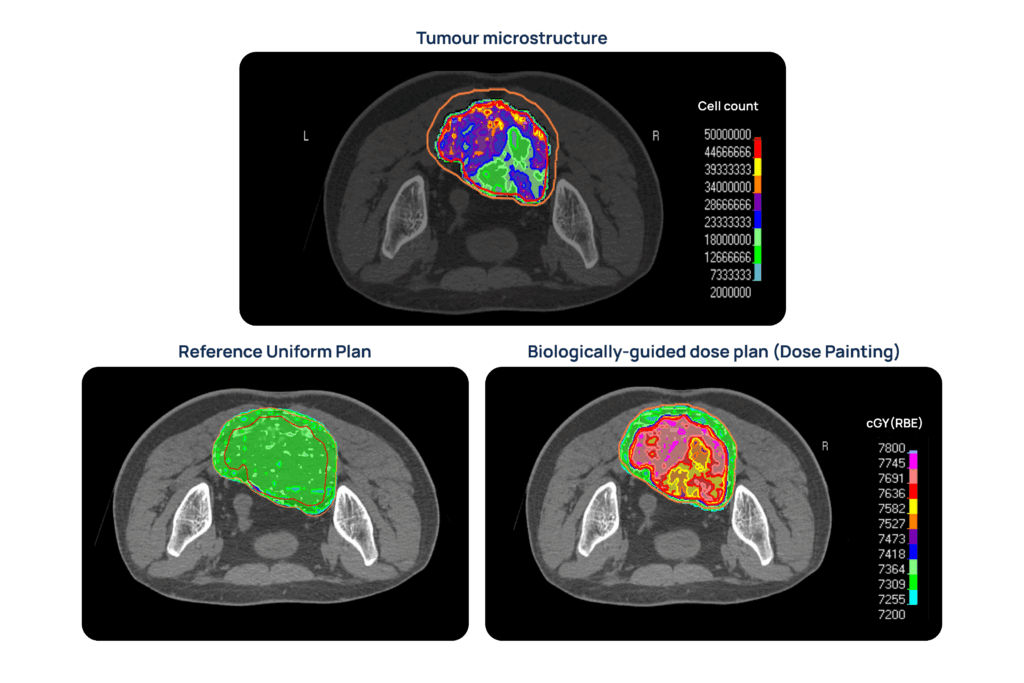

The AI and MC-based models trained in previous work packages will be applied to clinical datasets to derive personalized maps of tumor microstructure and radiobiology. Results will be compared with clinical information for correlation and predictive value. Moreover, the derived microstructural and radiobiological information will be used to implement personalized tumor control probability models towards biologically-guided dosimetric treatment plans.